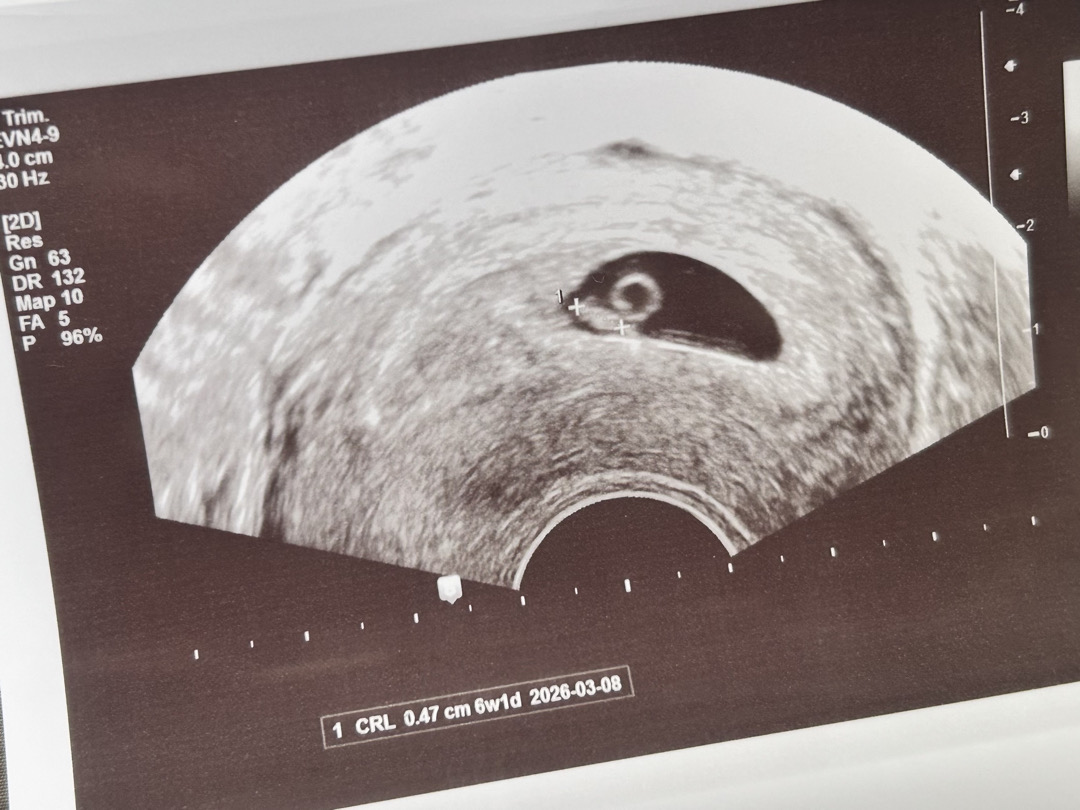

6주1일 초음파

6주1일 초음파 보고왔는데 애기가 원래 처음에는 저렇게 길죽한가요 -? ㅋㅋ 난황때매 달팽이 같기두 하구 임신증상이 하나도 없었어서 심장소리 들으니까 실감 나는거 같아요